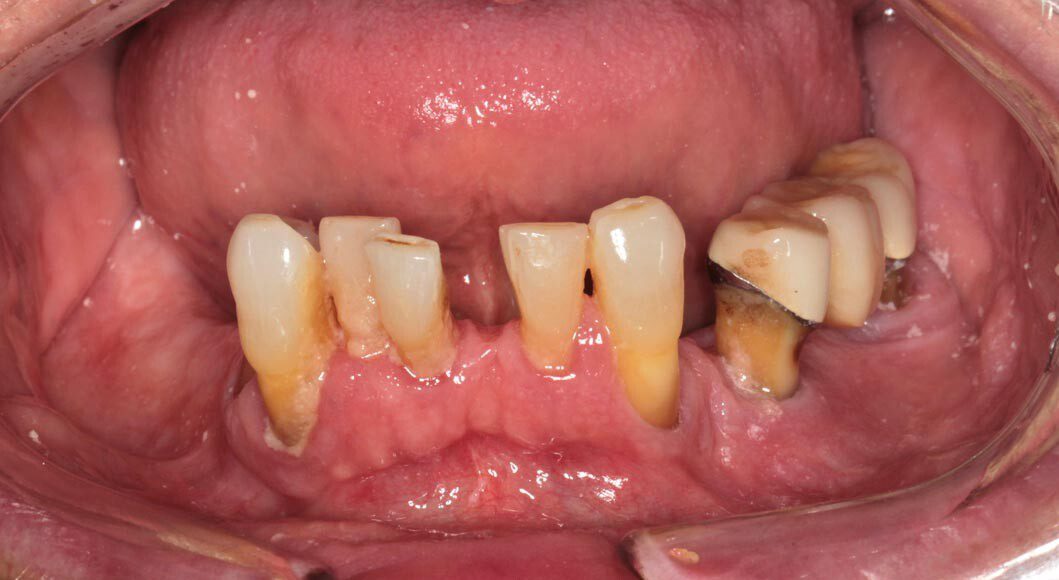

Pre-op, Panoramic x-ray. Note: Excellent bone in the upper front, reasonably good bone everywhere else.

Lower teeth extracted, some bone removal lower, 8 upper implants, 5 lower implants, lower immediate temporary bridge.